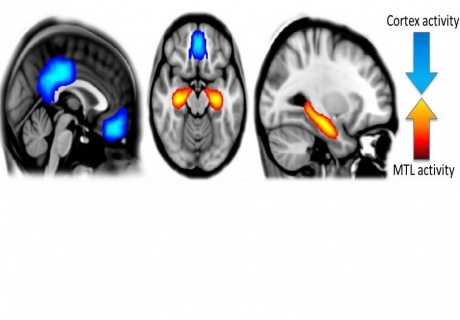

Reveló que, bajo los efectos de la psilocibina, aumentaba la actividad en la red más primitiva del cerebro, que está vinculada al pensamiento emocional.

Esta activación pronunciada implicó a varias regiones de dicha red al mismo tiempo, como el hipocampo (asociado a la memoria y la emoción) o la corteza cingulada anterior (relacionada con los estados de excitación).

Por otra parte, en los voluntarios sometidos al estudio se detectó una actividad más inconexa y descoordinada en la red cerebral vinculada al pensamiento avanzado, que hace posible, por ejemplo, que tengamos autoconciencia.

Reveló que, bajo los efectos de la psilocibina, aumentaba la actividad en la red más primitiva del cerebro, que está vinculada al pensamiento emocional.

Esta activación pronunciada implicó a varias regiones de dicha red al mismo tiempo, como el hipocampo (asociado a la memoria y la emoción) o la corteza cingulada anterior (relacionada con los estados de excitación).

Por otra parte, en los voluntarios sometidos al estudio se detectó una actividad más inconexa y descoordinada en la red cerebral vinculada al pensamiento avanzado, que hace posible, por ejemplo, que tengamos autoconciencia.

Actividad cerebral bajo el efecto de la psilocibina, con una reducción (en azul) de la actividad en las regiones cerebrales evolutivamente avanzadas, y una reducción (en naranja) en los centros de memoria y emoción. Fuente: Imperial College de Londres.